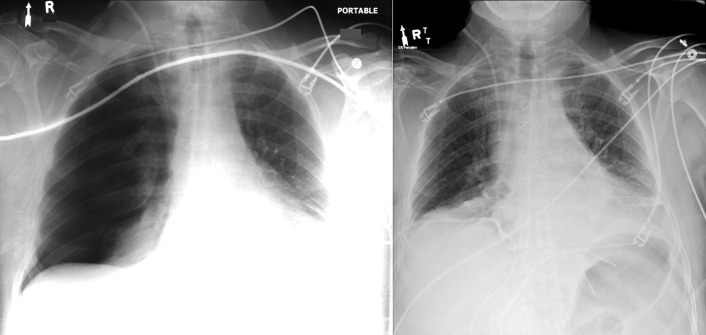

Central Venous Lines ( Figs. 22-1 to 22-13 )

To avoid mechanical irritation (from the catheter tip) and chemical irritation (from infusate) of the right atrium, the catheter tip of a central venous line should be further than the junction of the internal jugular vein and subclavian veins (near the level of the first thoracic rib). In addition, the tip should not be further in than the junction of the superior vena cava and right atrium. Central venous catheters that are intended to record central venous pressure should lie distal to the last venous valves (in the subclavian and internal jugular veins, 2.5 cm proximal to the beginning of the brachiocephalic vein) and before the right atrium. The ideal position of the tip of a peripherally inserted central catheter (PICC) line is in the distal superior vena cava.